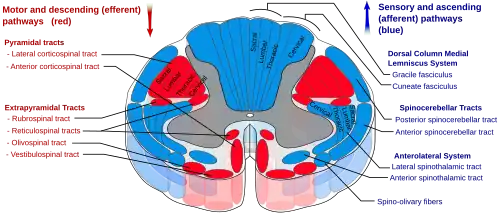

Восходящие нервные пути, соединяющие спинной мозг с таламусом, образуют спиноталамический путь, или спиноталамический тракт. В нём от спинного мозга к таламусу передаётся сенсорная информация о болевых, температурных и тактильных ощущениях, а также об ощущении зуда[14]. Спиноталамический путь подразделяется на две части: боковой, или латеральный, или дорсальный, спиноталамический путь[15], который передаёт информацию о болевых и температурных ощущениях, и передний, или вентральный, спиноталамический путь[16], который передаёт ощущения грубого прикосновения или сдавливания, надавливания[8].

В свою очередь, в боковом спиноталамическом пути выделяют эволюционно более молодой неоспиноталамический путь и более древний палеоспиноталамический путь. Первый состоит из большого количества тонких нервных волокон, которые быстро проводят болевые ощущения, а второй содержит меньшее количество более толстых и более медленно проводящих нервных волокон. Быстро проводящий неоспиноталамический путь играет большую роль в передаче в мозг хорошо локализованного ощущения острой боли непосредственно или вскоре после травмы, повреждения тканей, и в принятии организмом защитных мер, таких, например, как отдёргивание руки от горячего предмета. Более медленно проводящий палеоспиноталамический путь передаёт менее локализованную, более разлитую, тупую, давящую или сжимающую, реже жгучую или сверлящую хроническую боль, и играет большую роль в патогенезе различных хронических болевых синдромов[17][18].